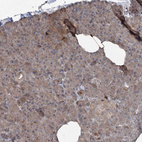

Immunohistochemical staining of human Cerebellum shows strong cytoplasmic positivity in Purkinje cells.